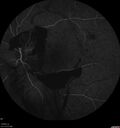

44 year old man About 2 months ago, the patient went to the beach with his family and noticed a hair in the eye sight in the left eye.  He was trying to rinse it out and saw that there was something not right.  He googled the problem and there was something about a floater and not being a big deal.  His vision was pretty good.  He was not getting regular eye examinations.  He did get checked in 2015 and got new glasses.  He had not been back since then for the last 5 years except for glasses. Last week the vision in the left eye got bad.  The vision in the right eye is fine.   VA OD: sc20/40 PH20/25 NscJ2 VA OS: sc20/63-2 PH20/32-1 NscJ1 IOP: TP: OD:17 OS:19

Proliferative Diabetic Retinopathy and vitreous hemorrhage left eye330 views44 year old man with type II diabetes for 14 years and no eye examinations in the last 5 years. VA 20/40 right eye and 20/60 left eye. Vision loss has been for about a week in the left eye.00000

44 year old man About 2 months ago, the patient went to the beach with his family and noticed a hair in the eye sight in the left eye.  He was trying to rinse it out and saw that there was something not right.  He googled the problem and there was something about a floater and not being a big deal.  His vision was pretty good.  He was not getting regular eye examinations.  He did get checked in 2015 and got new glasses.  He had not been back since then for the last 5 years except for glasses. Last week the vision in the left eye got bad.  The vision in the right eye is fine.   VA OD: sc20/40 PH20/25 NscJ2 VA OS: sc20/63-2 PH20/32-1 NscJ1 IOP: TP: OD:17 OS:19Â